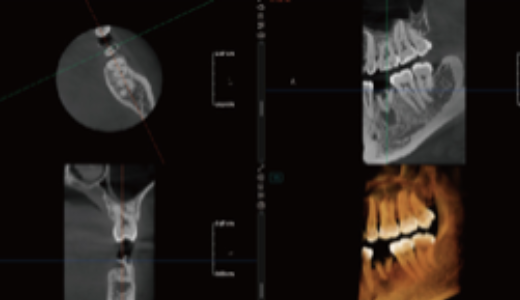

Algoritmo PD – Alta resolução espacial em TC até 2,8 lp/mm

Proporciona imagens com efeito de “textura natural”.

Previne eficazmente que pequenas lesões sejam ocultadas pela redução de ruído, reproduzindo com elevada fidelidade os detalhes do osso e dos tecidos moles.

Fornece aos clínicos informação diagnóstica mais precisa.